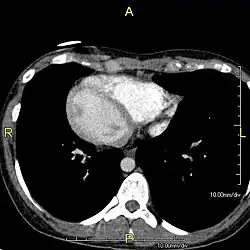

Diagnosis of situs inversus can be made using imaging techniques such as x-ray, ultrasound, CT scan, and magnetic resonance imaging (MRI).[9]

The condition affects all major structures within the thorax and abdomen. Generally, the organs are simply transposed through the sagittal plane. The heart is located on the right side of the thorax, the stomach and spleen on the right side of the abdomen and the liver and gall bladder on the left side. The heart's normal right atrium occurs on the left, and the left atrium is on the right. The lung anatomy is reversed and the left lung has three lobes while the right lung has two lobes. The intestines and other internal structures are also reversed from the normal, and the blood vessels, nerves, and lymphatics are also transposed.

Situs inversus is found in about 0.01% of the population, or about 1 person in 10,000. In the most common situation, situs inversus totalis, it involves complete transposition (right to left reversal) of all of the viscera. The heart is not in its usual position in the left chest, but is on the right, a condition known as dextrocardia (lit. 'right-hearted'). Because the relationship between the organs is not changed, most people with situs inversus have no associated medical symptoms or complications.[1]